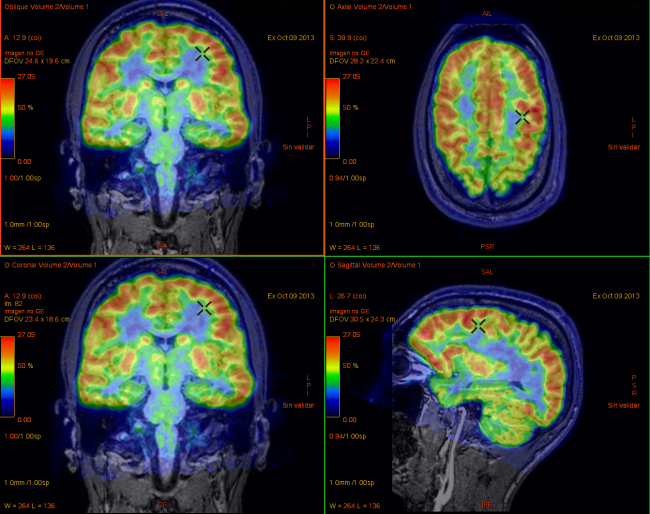

Tabla en la que el alumnado deberá de plasmar los parámetros de adquisición (protocolos de adquisición) de la imagen para las exploraciones cardíacas, músculo-esqueléticas y pulmonares.